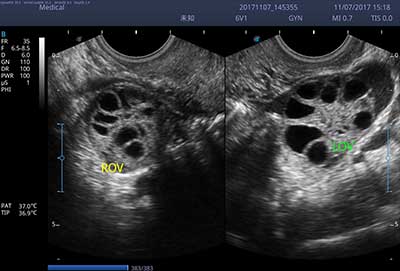

E3便携式彩色多普勒超声诊断系统拥有专业超声技术平台、高度集成化的硬件模块和结构设计、简便的操作流程、支持三探头接口全激活,兼顾了优质图像、轻便机身以及台便两用的临床使用需求。无论在常规超声科门诊检查,还是在急诊、麻醉、ICU、户外等各种应用场景。都能给您带来流程的操作体验。

• SR Flow 高分辨率血流